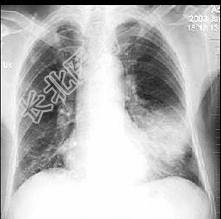

- 单项选择题男性患者,62岁, 咳嗽发热两天,痰中带血, 胸片检查如图,最合理的诊断是 ( )

A、左下肺炎症

B、左肺癌伴阻塞性肺炎

C、细支气管肺泡癌

D、左侧胸膜炎

E、左侧胸腔积液